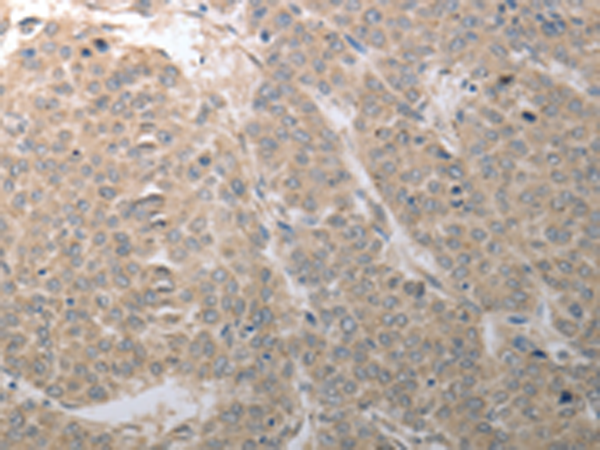

分类: 科研抗体货号: P11138别名:应用: IHC反应种属: Human